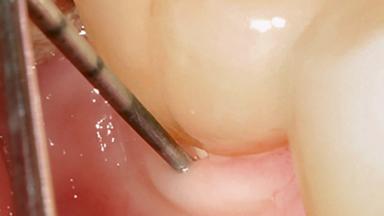

Treatment of Peri-Implant Mucositis at a Zirconia Implant